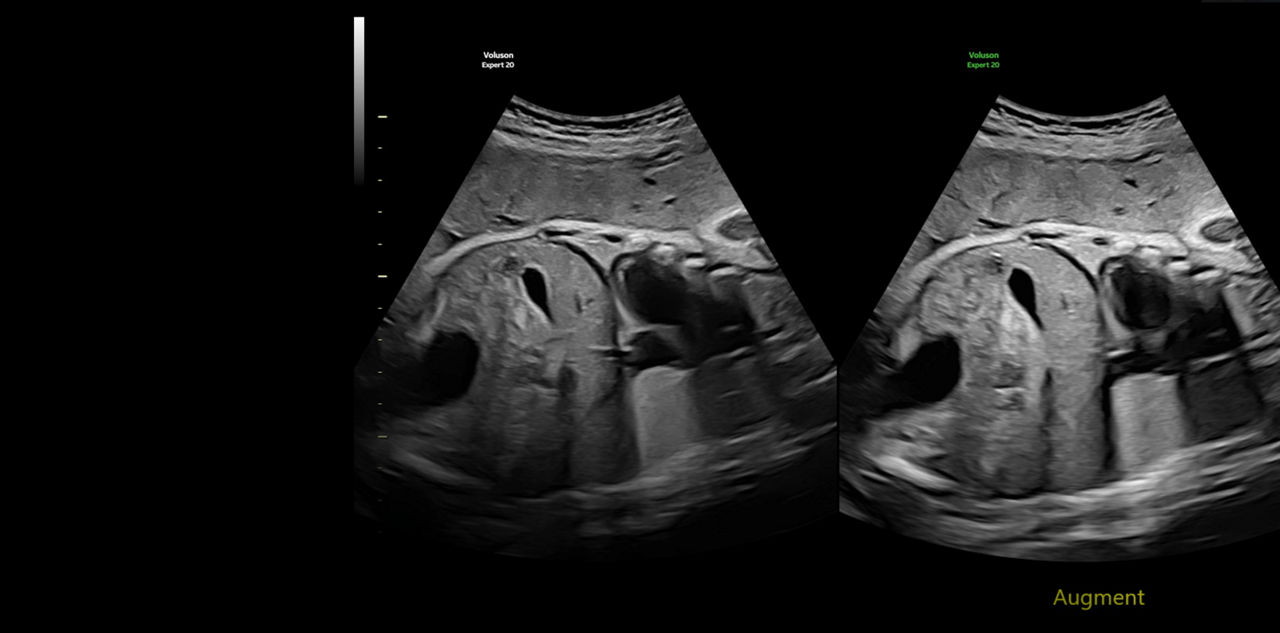

Generate spectacular 2D/3D and color Doppler images with increased penetration and stunning clarity, to help visualize critical details needed for diagnostic assurance. The Lyric Architecture unlocks new imaging and processing power to expand your imaging capabilities for years to come